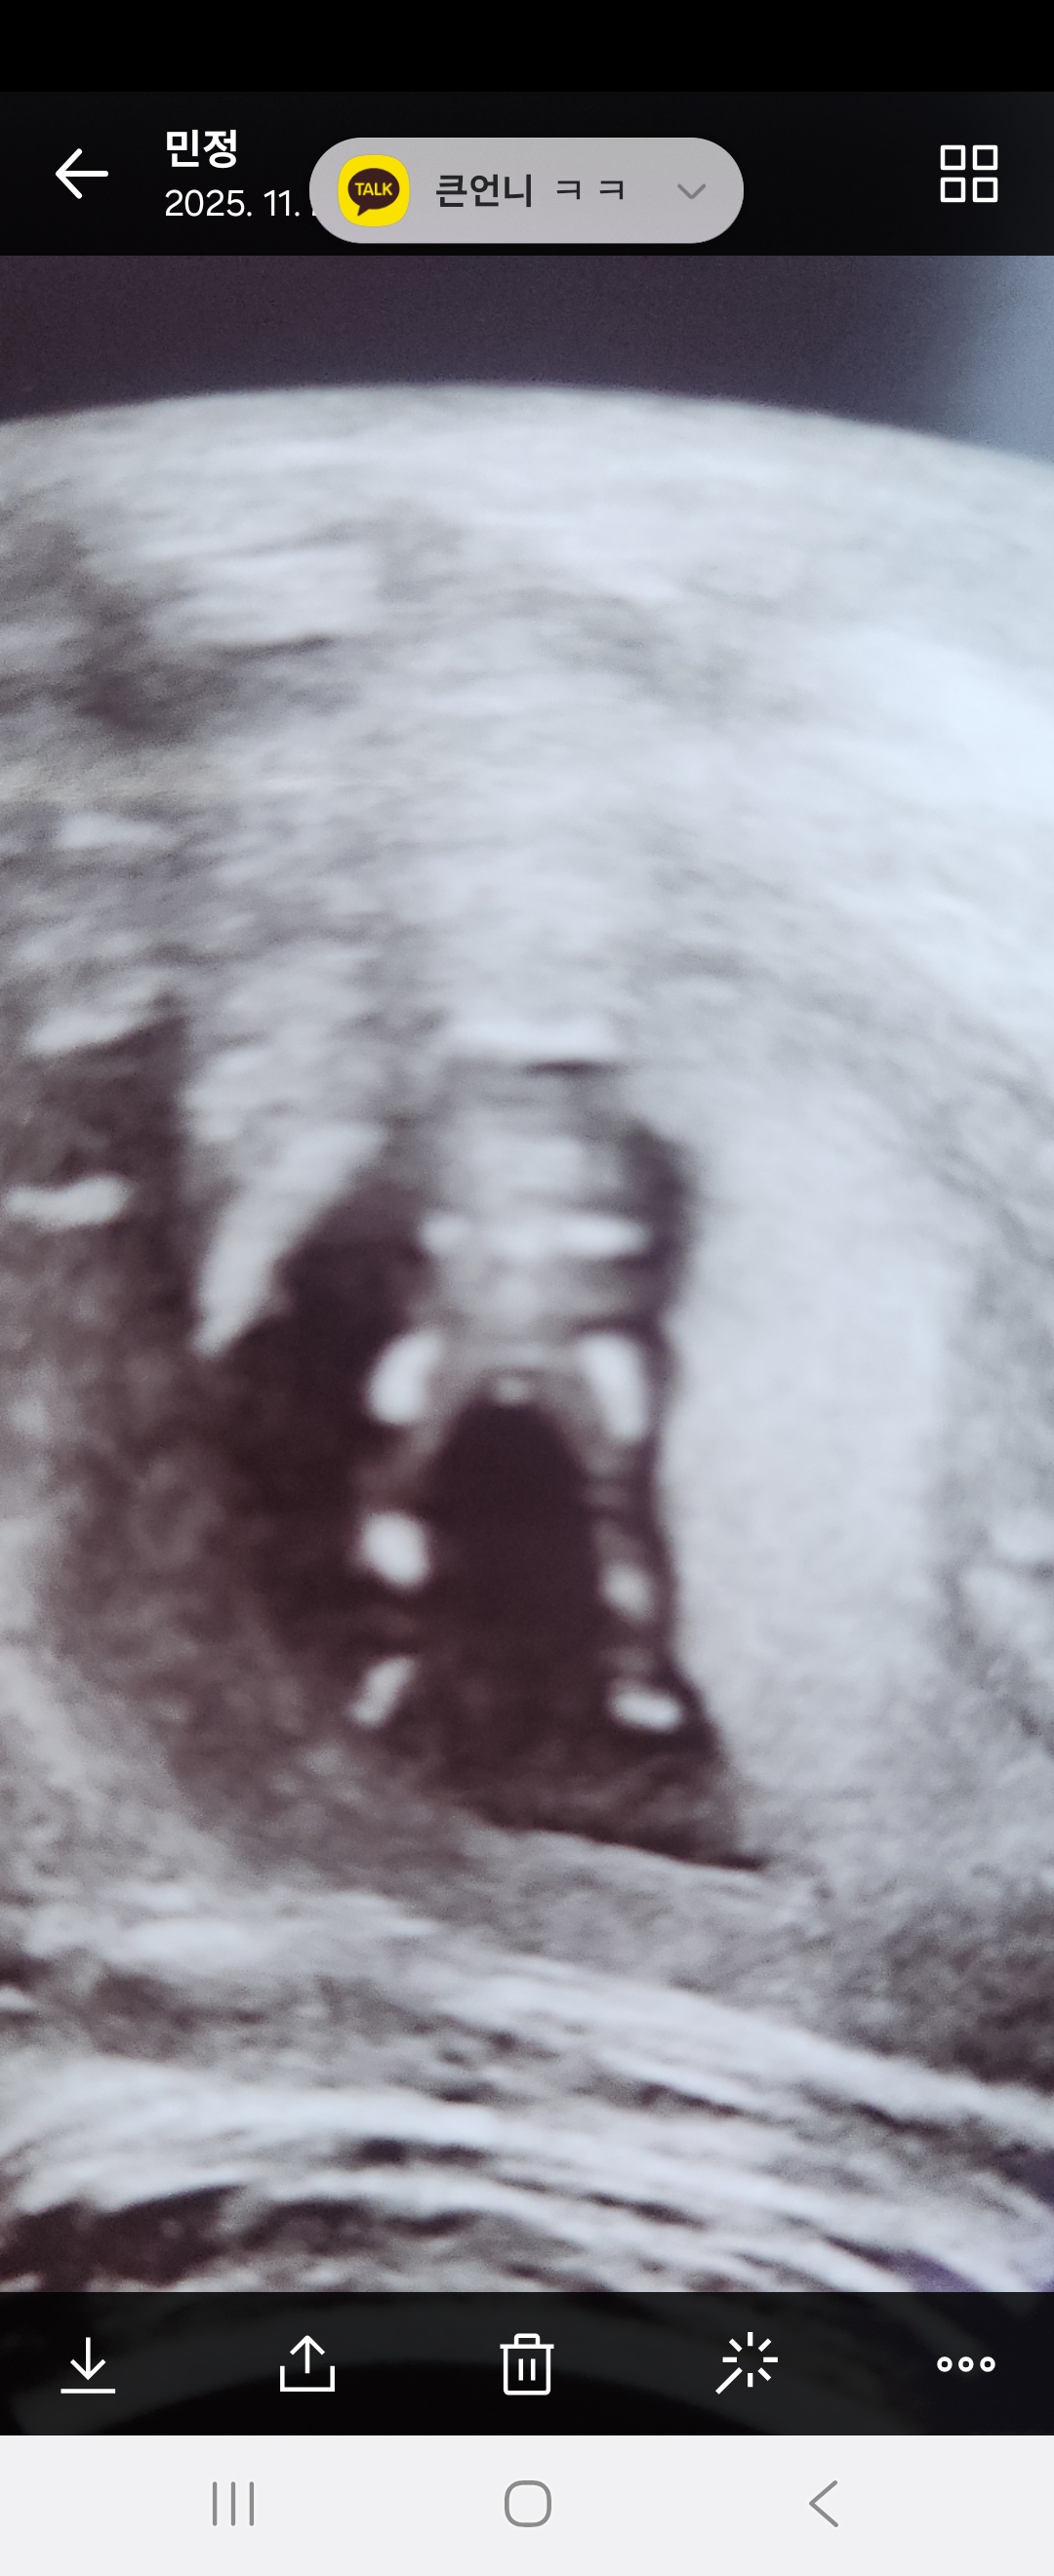

12주차 초음파사진인데 아들일지..ㅜㅜ봐주세요

다리 가운데 뭔가 떡하니 있는데 아직 성별은 모를시기라고 하시더라구요. 딸바라지 말라고 우리 콩이가 떡하니 보여주는 건지 아님 아직 기대를 저버리지 않아도 될지 ㅎㅎ 다들 보시기에 아들일까요?ㅠ

저 시기엔 모른다고 하더라고요 다리사이는 탯줄일 수 도 있대요!